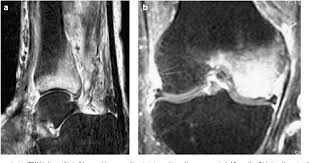

Mri Of Bone Marrow Edema Like Signal In The Pathogenesis Of Subchondral Cysts Osteoarthritis And Cartilage